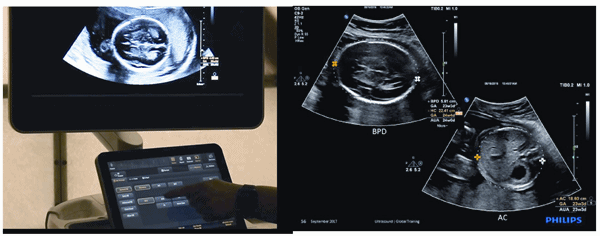

MaxVue high – definition display – Remarkable visualisation!

At the touch of a button, the new MaxVue high-definition display brings extraordinary visualisation of anatomy with 1,179,648 additional image pixels compared to a standard 4:3 display format mode. MaxVue enhances ultrasound viewing and provides 38 per cent more viewing area to optimise the display of dual, side/side, biplane, and scrolling imaging modes.